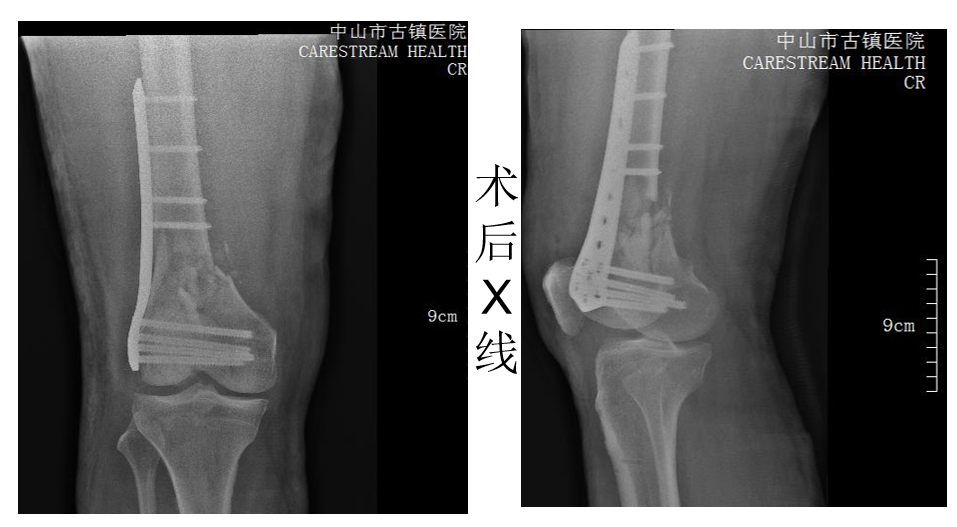

关节专业